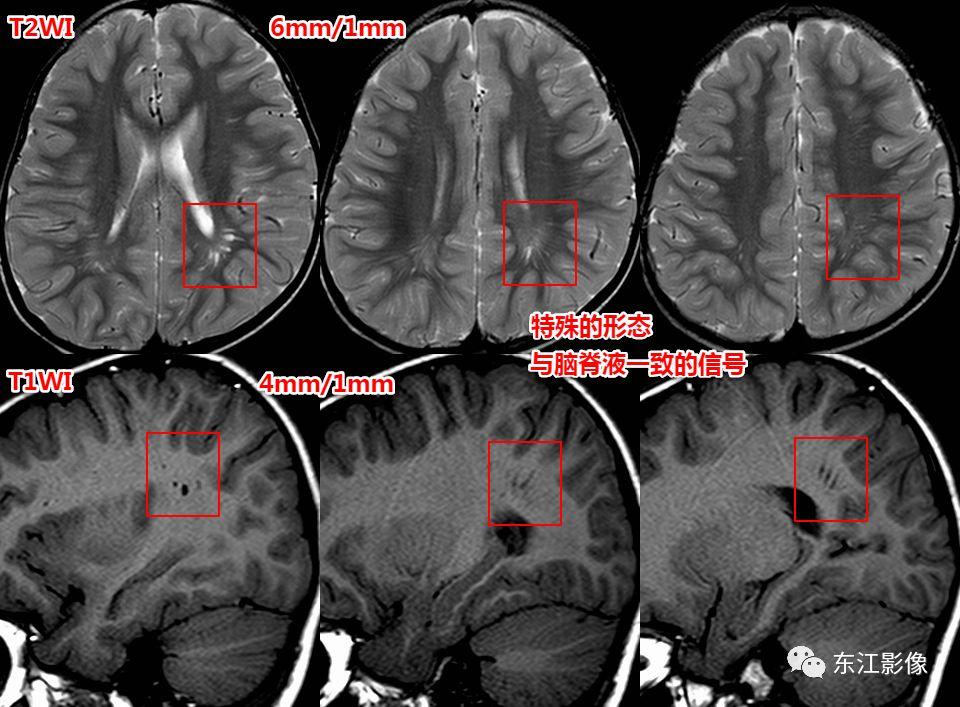

1. 扩大的血管周围间隙

扩大的血管周围间隙非常常见。

高场强、薄层扫描的话,每一个人都可见,无论老幼、男女。

影像诊断要点包括:

部位

- 常见部位:前穿质区,外囊区,额顶叶皮层下,中脑。——务必熟记!

- 其他部位:丘脑,颞枕叶皮层下,侧脑室周围白质,小脑。

形态

- 纺锤样,泪滴状。

信号

- 与脑脊液一致。

侧脑室顶区周围白质也是VRS的常见部位。

- 薄层扫描有助于这类小腔隙样灶的鉴别。